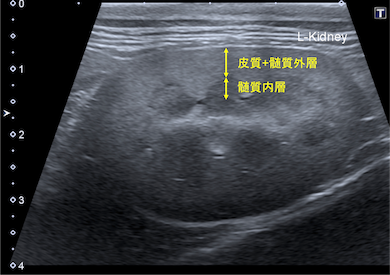

腎臓とは尿を作る臓器で、左右一対腰あたりに位置します。

通常は皮質・髄質・腎盂の3層からなっています

<腎臓は腰の辺りに左右1対ある>

<腎臓は外側から皮質・髄質・腎盂となっている>

<正常な腎臓の超音波画像>